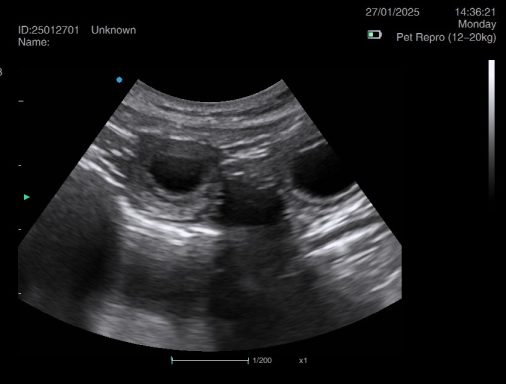

Ultrasound pregnancy scanning is a safe, non-invasive way to confirm pregnancy in dogs and cats, offering breeders and pet owners peace of mind and vital information to support responsible care. It allows us to detect gestational sacs, assess foetal development, and estimate litter size—all while ensuring the wellbeing of the animal.

Pregnancy can sometimes be detected as early as Day 18 post-mating, but scanning at this stage is not routinely recommended. Embryos are still developing and may not be clearly visible, and there is a natural risk of embryo resorption, which can lead to misleading or inconclusive results.

For the most accurate and reliable scan, we advise booking between Day 25 and Day 32, when pregnancy is more easily confirmed and foetal structures are clearer. If an early scan is performed and no pregnancy is detected, we offer a FREE complimentary re-scan after 7 days at the clinic to ensure clarity and support informed decision-making.

Our approach balances early insight with ethical care—always prioritizing the comfort of the animal and the accuracy of the results.